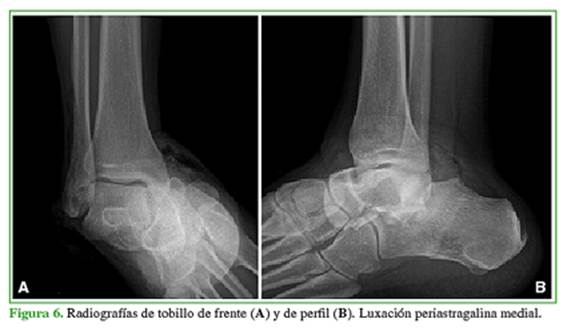

Hombre de 43 años que sufrió un traumatismo de tobillo derecho tras una caída desde un metro de altura. Consultó en la guardia de nuestro hospital el mismo día del traumatismo, tenía dolor, impotencia funcional y deformidad en dicho tobillo. Las radiografías mostraron una luxación periastragalina medial pura (Figura 6), por lo que fue sometido de urgencia a una reducción bajo anestesia (Figura 7).